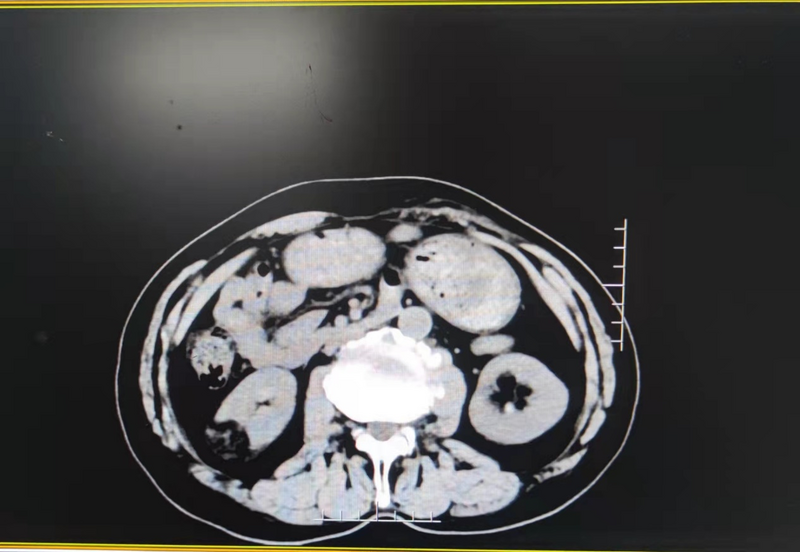

家住巢湖的陶先生,現(xiàn)年76歲,因“檢查發(fā)現(xiàn)右腎占位1月”就診于當(dāng)?shù)蒯t(yī)院,既往有高血壓、腦梗塞多年,平時長期服用多種降壓藥和抗凝藥物,查泌尿系CT顯示右腎占位性病變,約3*3cm大小。當(dāng)?shù)蒯t(yī)院檢查后,醫(yī)生建議行手術(shù)治療?;颊咭蚋啐g、基礎(chǔ)病較多,加之長期服用抗凝藥物等原因,手術(shù)心存顧慮,想盡可能通過創(chuàng)傷較小的方式解決。患者家屬經(jīng)網(wǎng)上查詢后發(fā)現(xiàn)我院較早開展單孔腹腔鏡技術(shù),且該項技術(shù)業(yè)已成熟,遂來我院泌尿外科就診。泌尿外科副主任王龍信接診后仔細(xì)閱片,發(fā)現(xiàn)患者存在右側(cè)腎臟占位,腫瘤呈外生性生長,可行單孔腹腔鏡手術(shù)切除腫瘤,保留患側(cè)腎臟,最大程度保留腎臟功能,遂收住入院。